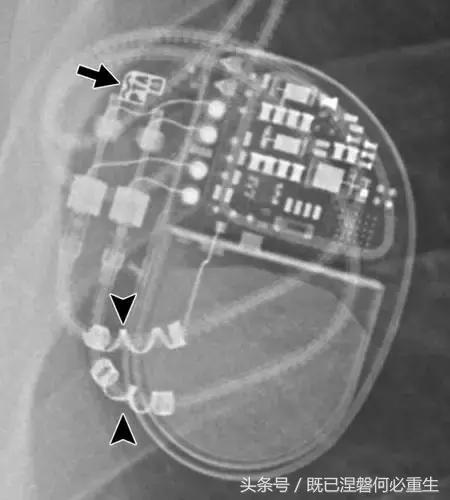

许多公司制造起搏器和ICD,每家公司生产一个专用设备(BOS程序员)进行适当的测试。程序员是手提箱尺寸的机器,通常重量为10-12公斤,当需要进行系统检查时,必须携带给患者。因此,识别制造商的胸部射线照相报告可以帮助临床医生必须选择哪个程序员到床边。多数厂家上放置他们的发电机易于识别公司标识,除了特定于设备的标识符(图4)。例子包括St. Jude Medical(SJM); Pacesetter,Guidant(GDT); 心室起搏器公司(CPI); 美敦力(M); Biotronik,Intermedics; 和ela(Sorin)。许多制造如今这些标志是由其他公司(国有公司的图4)。负责设备的临床医生熟悉制造商和测试每个设备所需的正确编程人员。在放射学报告中只需要标识的标识。

图。 4 制造商标志。A -H,显示的是来自St. Jude Medical(A),Pacesetter(由St. Jude Medical拥有)(B),Guidant(由Boston Scientific拥有;目前的Boston Scientific徽标[BOS] (C),Cardiac Pacemakers Incorporated(由Boston Scientific拥有)(D),Medtronic(E),Biotronik(F),Intermedics(由Boston Scientific拥有,但需要特殊程序员) )。 许多制造这些标志的公司现在由其他公司拥有。 当前波士顿科学(BOS)标志如图8B(H)所示。 目前与每个标识相关联的公司的知识不是必需的,并且仅为一般信息提供。 对放射学报告重要的是识别标志本身。 标志可以是金属密度或较不透明的,并且更难以可视化。 如果存在,标志附近的字母和数字是设备特定的标识符。